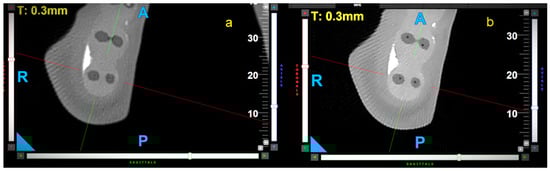

All file movements resulted in a significant reduction in wall thickness over the entire length of the samples. The control group presented the highest WTR in the apical (WTR = 0.21) and middle (WTR = 0.19) parts of the samples. The differences between the movements were statistically significant in the apical and middle parts of the root (3 mm: p < 0.001; 6 mm: p = 0.007). OTR movement caused the highest WTR in the coronal part of the samples (WTR = 0.13), but the differences between these movements were not statistically significant (p = 0.056). Representative CBCT horizontal slices of samples at 3, 6, and 9 mm from the radiological apex are shown in Figure 3, Figure 4 and Figure 5.

Figure 3. Representative CBCT axial—horizontal slices of samples at 3 mm from apex, before (a) and after (b) canal preparation—rotary movement. The letters A, P, R indicate sides—anterior, posterior, and right respectively.